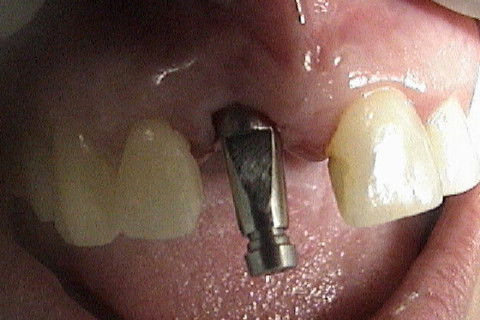

Colocação de parafuso de laboratório para se saber se a prótese será cimentada ou parafusada. (se o parafuso sair na face palatina, será parafusada, se sair na incisal ou vestibular, será cimentada).

Vista oclusal do mesmo parafuso